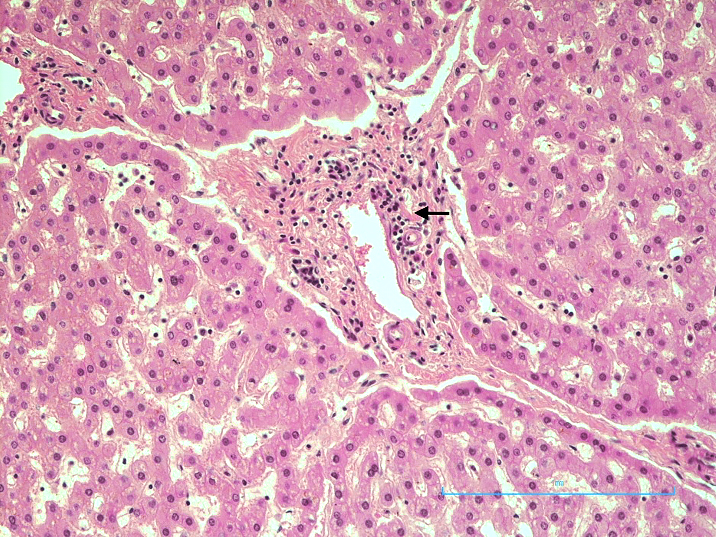

Liver: There was a moderate infiltrate of lymphocytes within the portal triad (Figure 2).

A moderate portal triaditis was also a feature seen in this patient. This might represent part of the inflammatory response that occurs to SARS-CoV-2 infecting pericytes in vessels in the portal tract. The portal triaditis might be responsible for the abnormal liver function seen in COVID-19.36